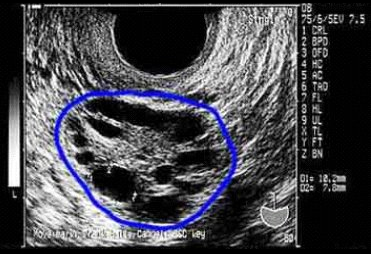

SOP 4

Síndrome de Ovarios Poliquísticos, cuales son sus riesgos.